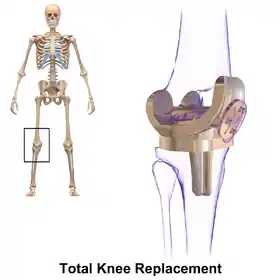

Knee

Knee replacement involves exposure of the front of the knee, with detachment of part of the quadriceps muscle (vastus medialis) from the patella. The patella is displaced to one side of the joint, allowing exposure of the distal end of the femur and the proximal end of the tibia. The ends of these bones are then accurately cut to shape using cutting guides oriented to the long axis of the bones. The cartilages and the anterior cruciate ligament are removed; the posterior cruciate ligament may also be removed but the tibial and fibular collateral ligaments are preserved.[6] Metal components are then impacted onto the bone or fixed using polymethylmethacrylate (PMMA) cement. Alternative techniques exist that affix the implant without cement. These cement-less techniques may involve osseointegration, including porous metal prostheses.